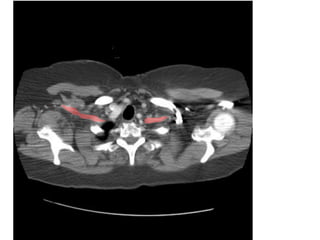

Figure 26. Xảo ảnh dải sọc (streak artifact) ở bn nữ 35 tuổi, có đau

ngực.

- Xảo ảnh dải sọc do đậm độ chất cản quang cao trong tĩnh mạch chủ

trên. (mũi tên). Xảo ảnh này có thể nhận biết được do hướng lan và vị trí

“không phải giải phẩu” (nonanatomic) của nó.

34